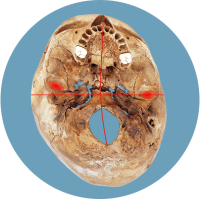

Das größte Problem besteht darin, dass der Kopf in seiner Struktur verändert wird – die Schädelbasis wird schief. Davon sind hauptsächlich die Stellung der Ohren (Gleichgewichtsorgane), die Kiefergelenke (Zahnfehlstellungen) und Halswirbelkörper betroffen. Kritisch wird dies spätestens, wenn sich die Kinder zum Ende des 1. Lebensjahres aufrichten und eine schiefe Wirbelsäulenhaltung entwickeln.

Die verschobene Position der Gleichgewichtsorgane ist durch die roten Kreuze gekennzeichnet.

Fehlerhafte Informationen aus den verschobenen Gleichgewichtsorganen bzw. dem Nackenrezeptorenfeld beeinflussen die Verarbeitung im Gehirn und können zu einer Fehlhaltung der Wirbelsäule führen.

Dadurch wird der Kopf intuitiv schief gehalten, der Körpersinn entwickelt sich nicht richtig, was Auswirkungen auf die motorische Entwicklung und Körperwahrnehmung nach sich zieht.